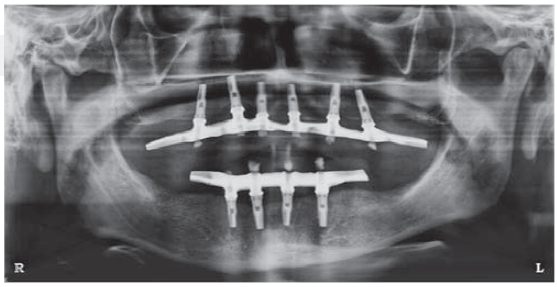

After six months, radiographic evaluation was conducted, which revealed preserved bone tissue surrounding the implants and no signs of complications. After this, surgical exposition and healing screw placement was undertaken and bone integration of all implants was observed.

Implant supported prosthesis

Two weeks later, manufacture of implant-supported prosthesis for both jaws was undertaken. Both prostheses were of hybrid design (full bone anchorage).

The case was followed for 18 months; no complications were observed and final result was functional and aesthetically satisfactory.

Likewise, in the case described in the present article, it was decided to wait for six months before subjecting the implants to functional loads. Moreover, all implants were bone-integrated and were loaded without any complication at an 18 month follow-up period. This result concurs with the survival and success rates of implants placed with the split crest technique reported by other authors.13,14,18,19